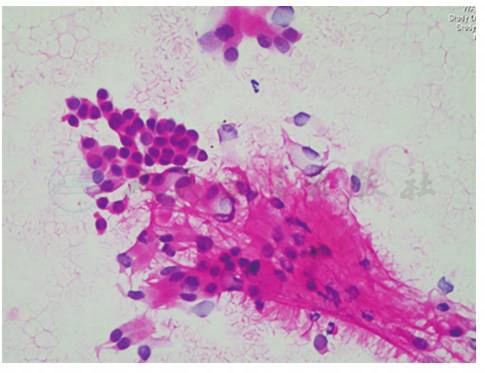

图12 左主支气管新生物涂片

血性背景中可见少量支气管黏膜上皮细胞、散在淋巴细胞及中性粒细胞(HE染色,400×)